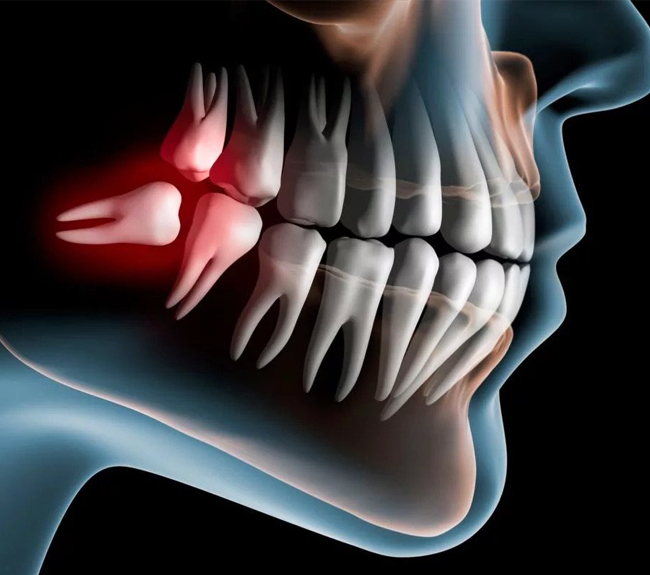

Wisdom Teeth Extraction

Wisdom Teeth Troubles? Let Us Preserve Your Smile's Brilliance

Relieve Toothache With Wisdom Tooth Extraction

What is Wisdom Teeth Extraction?

Wisdom teeth extraction is the surgical removal of the third molars to address potential oral health issues.

Why Need Wisdom Teeth Extraction?

Addressing potential dental problems and preserving oral health through timely wisdom teeth extraction.

What Are Our Procedures For Wisdom Teeth Extraction?

Assessment and Planning

A thorough examination of the patient's oral health, including X-rays and imaging, evaluates the position, condition, and potential complications.

The Procedure

Skillful wisdom teeth extraction using surgical techniques, such as sectioning or bone removal, while ensuring patient comfort and safety.